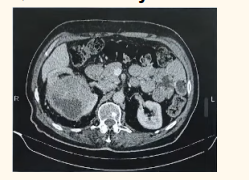

Identify the disease shown in the image: